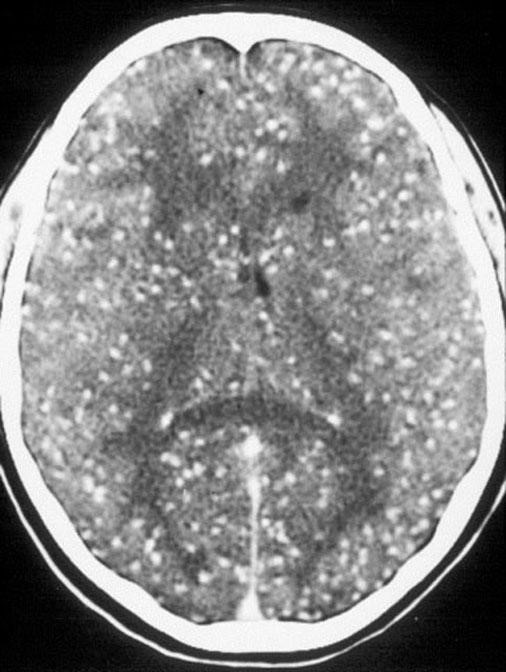

multiople March 15, 2017 506 × 672 AM Report 03/07/17: Neurocysticercosis Multiple cysts. Reference: Medscape Share this: Share on X (Opens in new window) X Share on Facebook (Opens in new window) Facebook Like Loading...